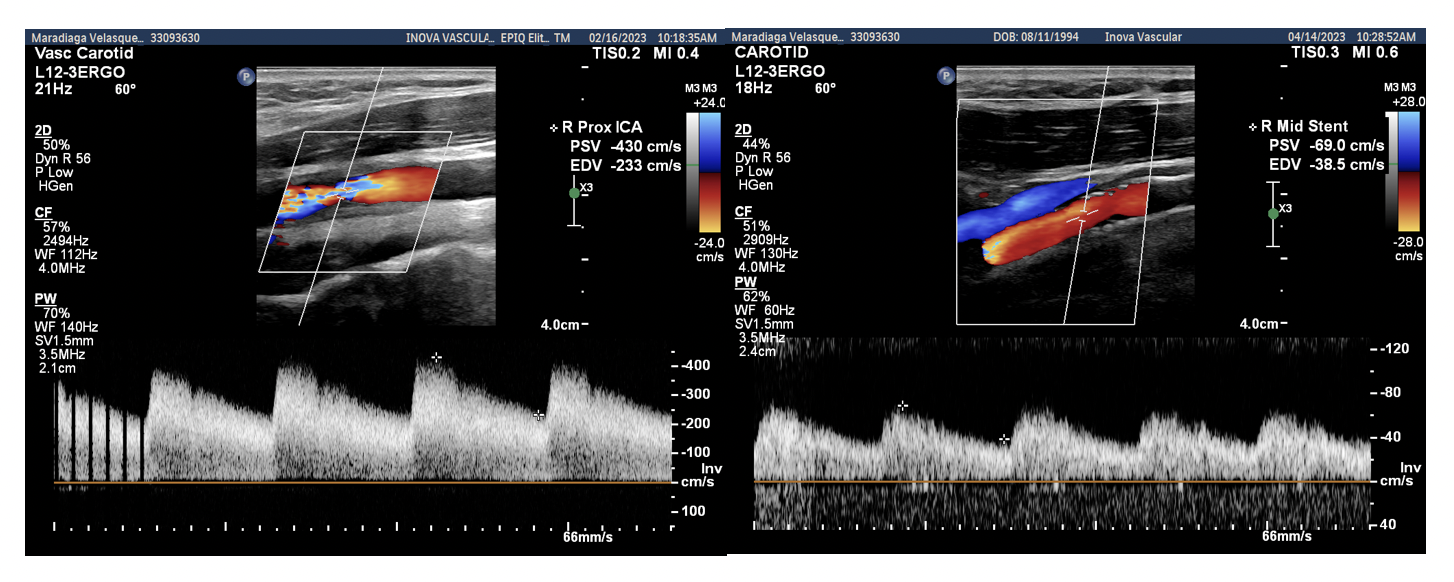

The patient returned to normal motor function of all extremities and normal speech function 3 months after the TCAR procedure. A duplex ultrasound exam confirmed a widely patent stented right CCA and ICA with no residual stenoses. Rheumatology service suggested no immune suppression treatment. The level of inflammatory markers was normal. Figure 4 depicts the stent in the right image with the peak systolic velocity and end-diastolic velocity measurements included.